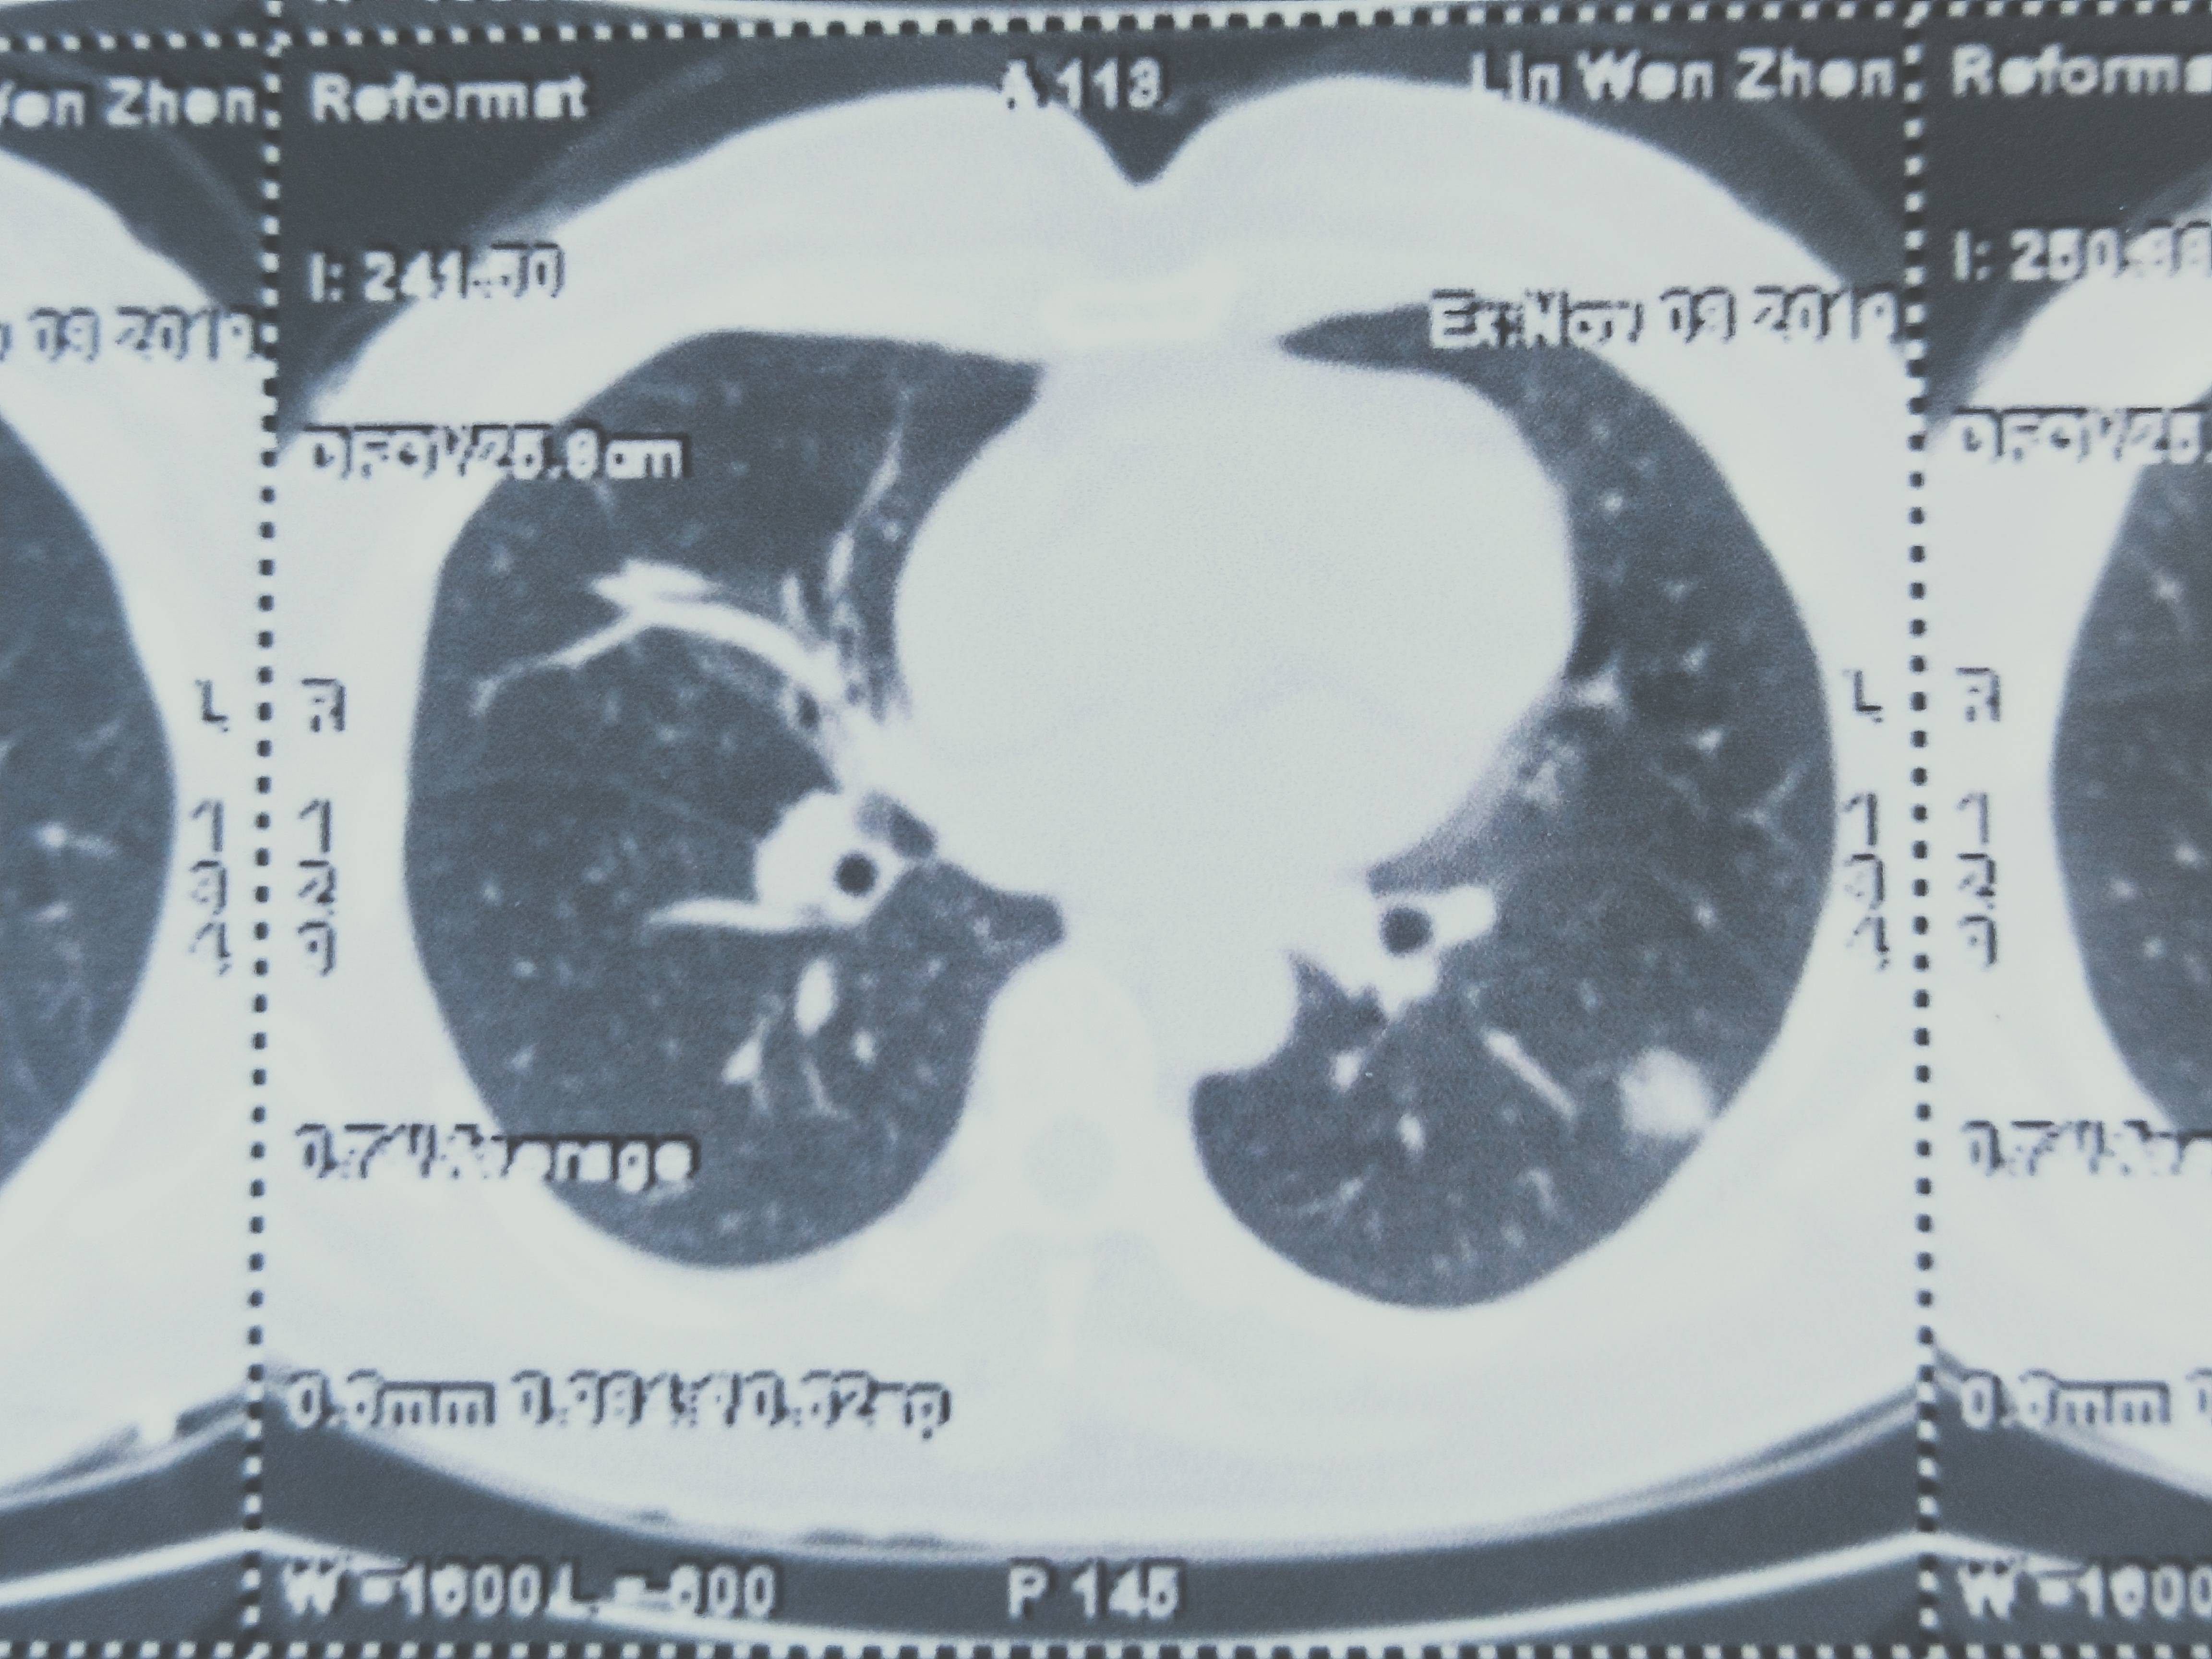

肺腺癌,胸膜粘连,没做弹力纤维染色

母亲术后病理是肺腺癌,CT上也写了与邻近胸膜粘结,但是手术医生没有把胸膜取下来做病理。不知道有没有胸膜侵犯。怎么办啊?其它没有转移,就怕有胸膜侵犯。术后没有治疗。